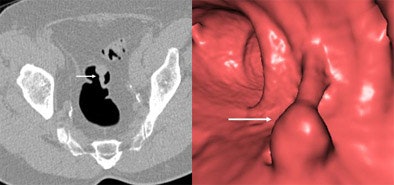

![]() |

| Abnormality measuring 7 mm in the cecum was seen at screening virtual colonoscopy but not conventional colonoscopy. The VC finding was initially thought to be a polyp based on 3D image (left). However, confirmatory 2D image at right shows a telltale gas bubble indicating residual fecal material. If the density of the material had been homogeneous and the gas bubble absent, it might have been misinterpreted as a polyp in both 2D and 3D. Images courtesy of Dr. Michael Macari. |